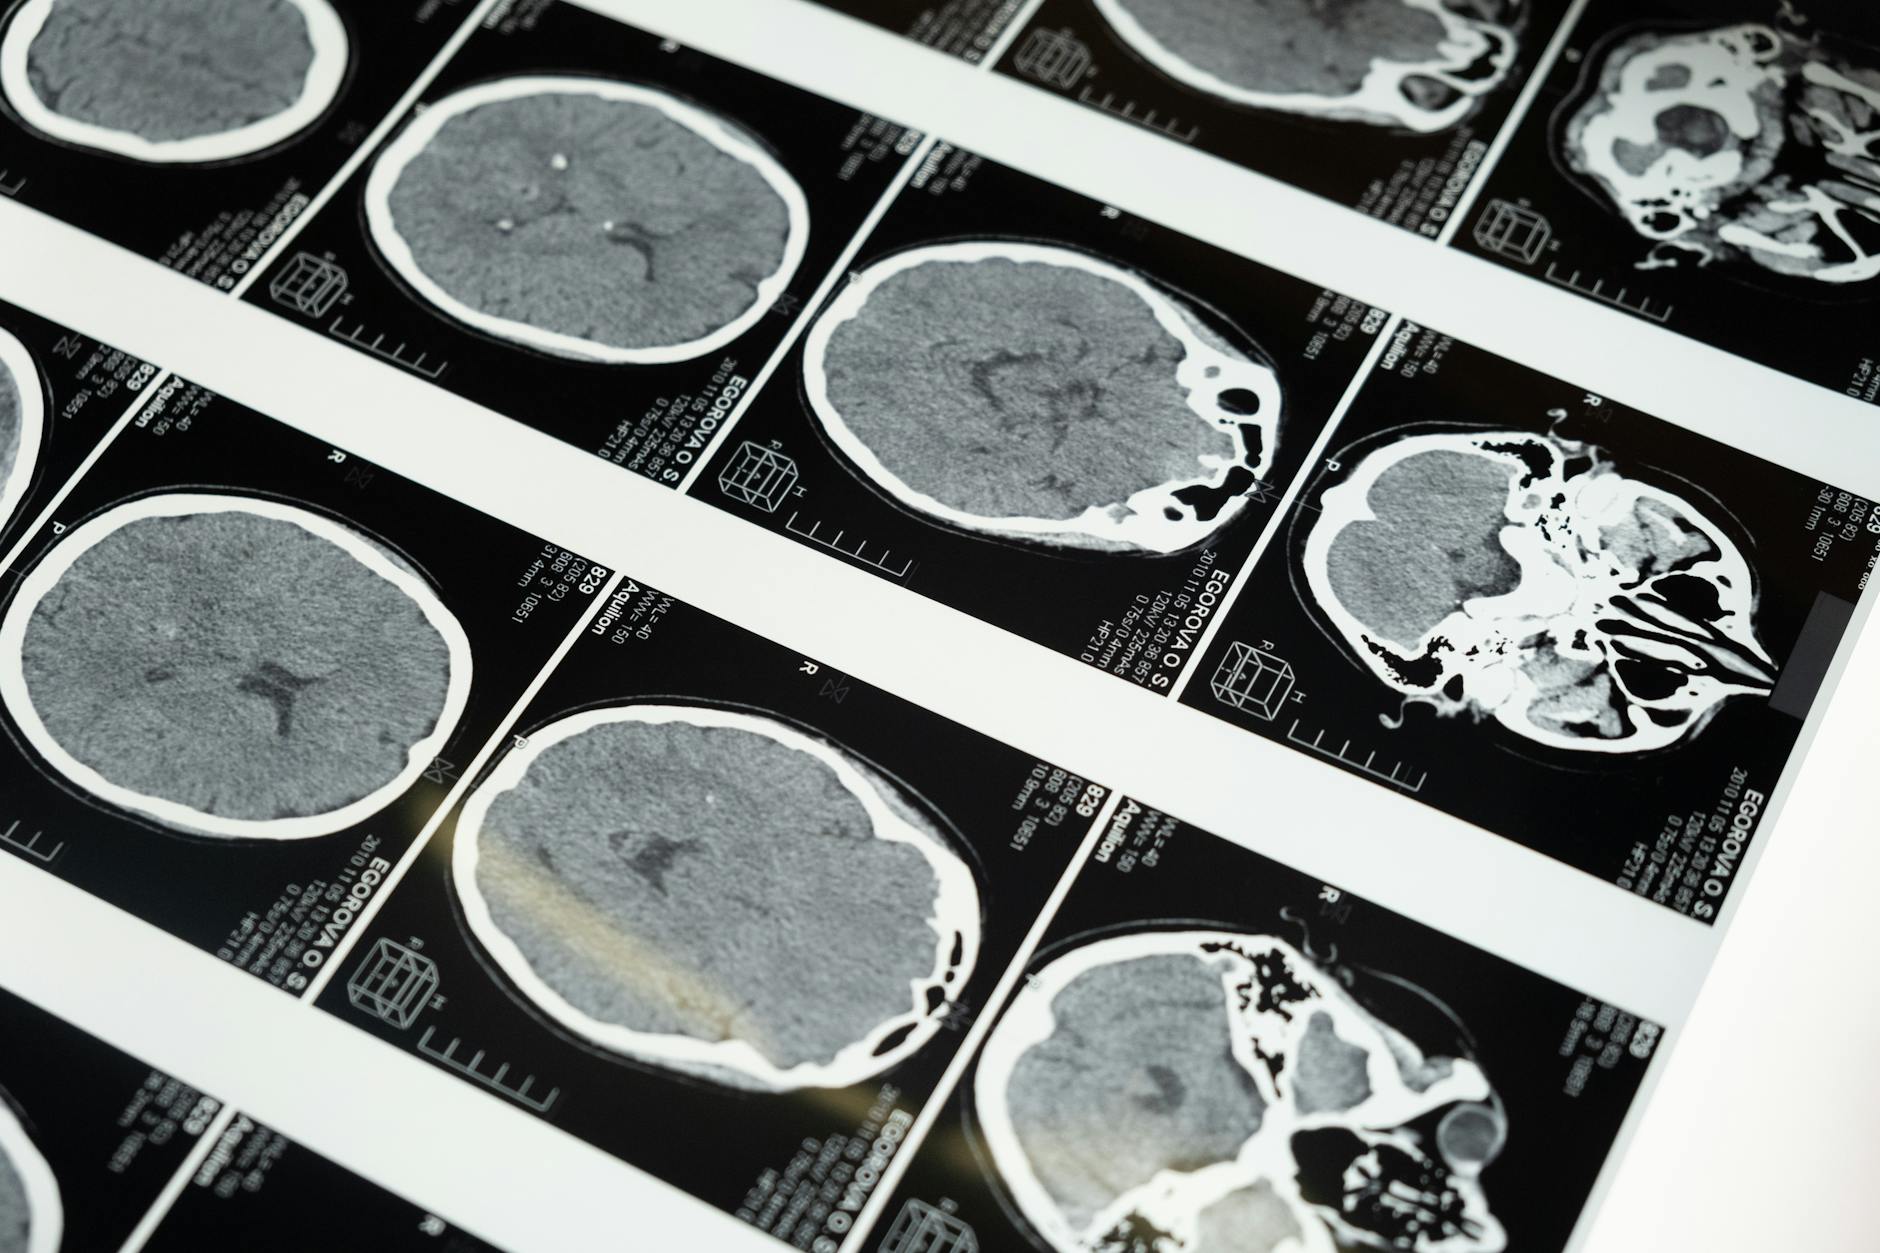

Si rivolge quindi a pazienti con cerebrolesioni acquisite (ictus ischemico o emorragico, trauma cranio-encefalico, anossia…) o affetti da patologie neurodegenerative (demenze di vario genere, sclerosi multipla…).